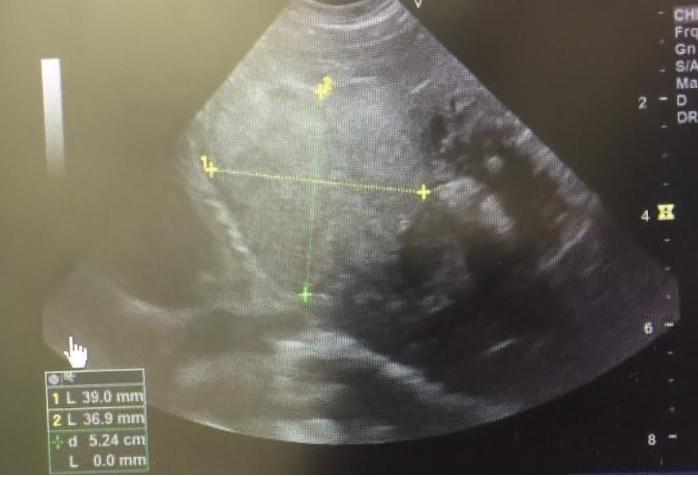

検査をしたところ肝臓に約4cmの腫瘍があることが発覚したんです。

※以下エコー画像